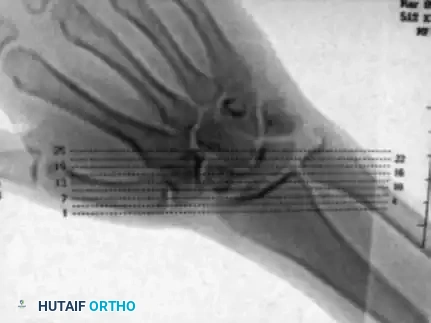

Established nonunions of scaphoid fractures frequently undergo volar resorption and comminution. Because the scaphoid spans the proximal and distal carpal rows, loss of volar cortical support leads to a predictable pattern of collapse: the distal pole flexes, and the proximal pole extends alongside the lunate. This results in shortening, radial deviation, and a dorsal convexity known as the "humpback" deformity.

This pathoanatomy drives a dorsal intercalated segment instability (DISI) pattern, visible on lateral plain radiographs as an increased scapholunate angle and an extended lunate posture. Failure to correct this deformity during grafting leads to altered carpal kinematics, restricted range of motion, and inevitable radiocarpal arthrosis.

Amadio et al. and Cooney et al. refined this concept, proposing anterior (volar) wedge grafting specifically for nonunions presenting with:

* A scapholunate angle greater than 60 degrees.

* An intrascaphoid angle greater than 45 degrees.